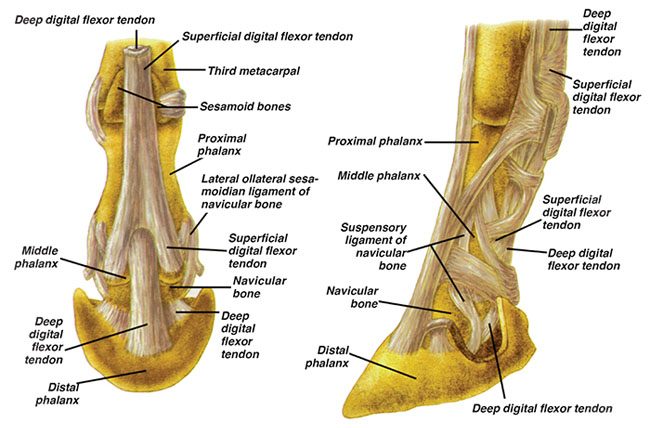

Of major importance to mobility of the limbs, Goble says the navicular bone “lays the groundwork of movement by serving as a conduit between the coffin bone and the deep digital flexor tendon (DDFT).” Defining it as a sesamoid bone (similar in nature to the sesamoid bones located behind the fetlock), it is positioned behind the coffin bone and below the small pastern bone, with the DDFT running underneath.

“As the navicular bone articulates with the coffin joint, or distal interphalangeal joint, on its anterior (front) surface to provide a smooth caudal (posterior) surface over which the deep flexor tendon glides,”…